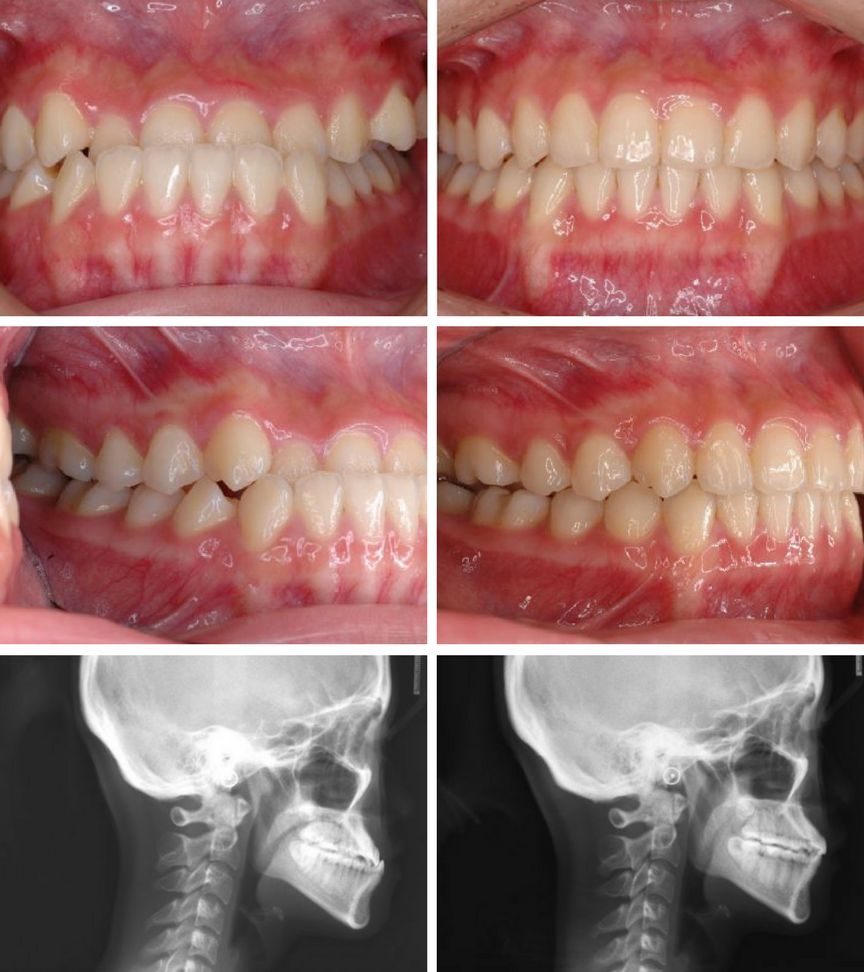

CASE 2

关键词

过咬合、凸嘴

这个是我们常说的龅牙(天包地),除了上排牙突出之外其他牙齿也很整齐没毛病。

这个妹妹也是拔掉了左右两颗第一前臼齿,把整排上牙往后推,总共是35个牙套,时长10个月,效果显著。

35

10

CASE 3

地包天、虎牙突

这是一个地包天的案例,其实从侧面脸来看不是特别明显,但是牙齿可以明显看到咬合状态下是下牙比上牙前,张嘴不好看。

这是一个小女生,这种地包天的程度不算严重,没有拔牙,一共40个牙套,14个月完成~

其实我们做过很多地包天的案例都没有拔牙的~也有少数cases是比较严重的地包天,需要拔掉下排两颗牙齿把下排推进去很多。比如下面这个姑娘。

40

14